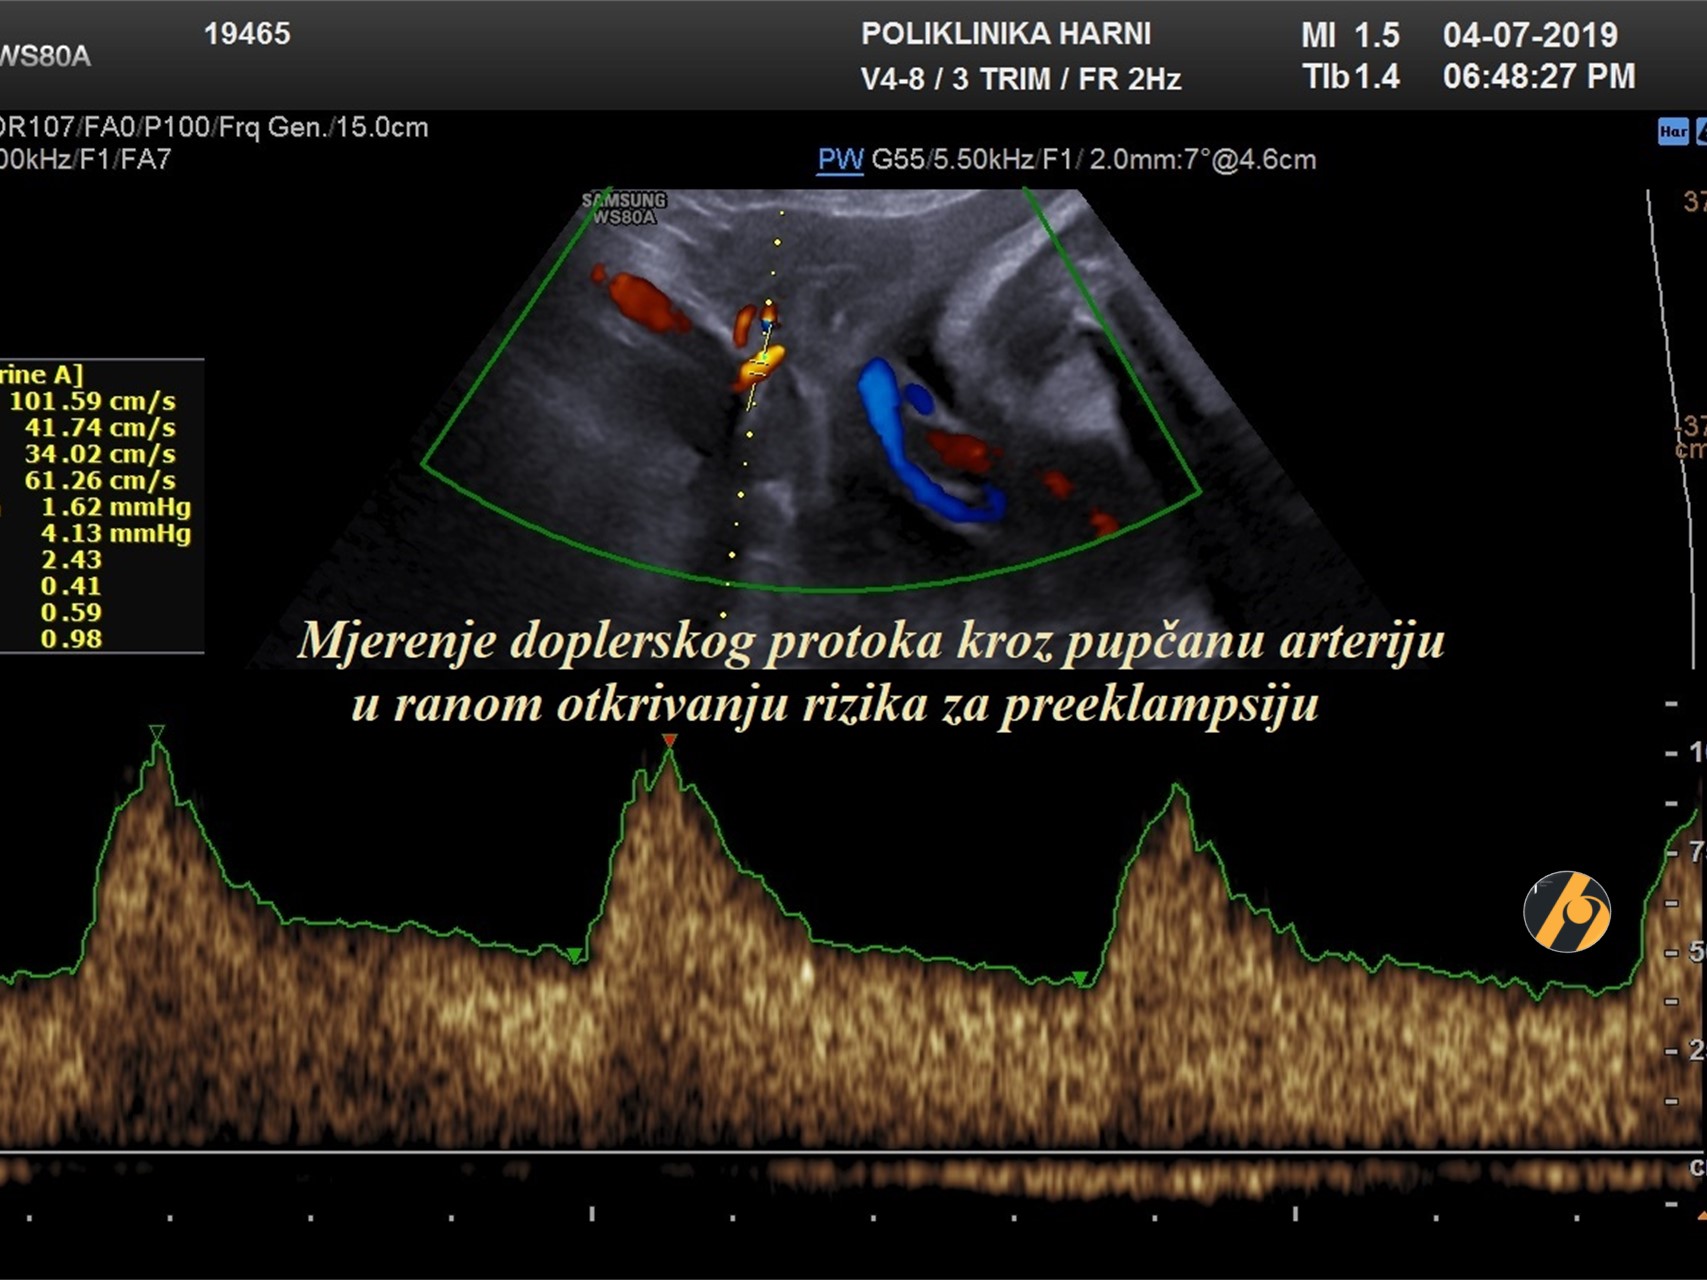

Dopplerska mjerenja

Dopplerska mjerenja protoka u fetoplacentarnoj jedinici nije dio rutinskog ultrazvučnog pregleda u drugom tromjesečju. Nema dovoljno dokaza koji bi podupirali općenitu uporabu Dopplerskih mjerenja protoka uterinih ili umbilikalnih arterija u probiru niskorizičnih trudnoća. Neki znanstvenici preporučuju rutinski pregled obojenim Dopplerom između 30. - 34. tjedna trudnoće kod svih trudnica, osobito ukoliko fetus ne napreduje kako se očekuje. Mjerenje indeksa protoka kroz fetalne krvne žile i pupčanu arteriju može pretkazati fetalnu patnju i do mjesec dana ranije, uslijed nepravilnost razvoja i/ili funkcije fetoplacentarne jedinice.

Zbog specifičnosti u razvitku fetomaternalnih krvnih žila Dopplerska mjerenja (obojeni / kolor Doppler) protoka u pupčanim arterijama rade se tek nakon 20. tjedna trudnoće. Izuzetak je sumnja na anomalije fetalnog srca ili krvnih žila, kao i zastoj rasta. Dopplersko mjerenja protoka u krvnim žilama maternice je korisna pretraga u rizičnim trudnoćama, jer ukazuje na funkcionalnost fetoplacentarne jedinice i rizik za preeklampsiju.